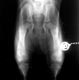

| Der selbe Hund in der

gehaltenen Aufnahme: Deutliche Subluxation der Femurköpfe. Distraktionsindex 0,50 rechts und 0,47 links |